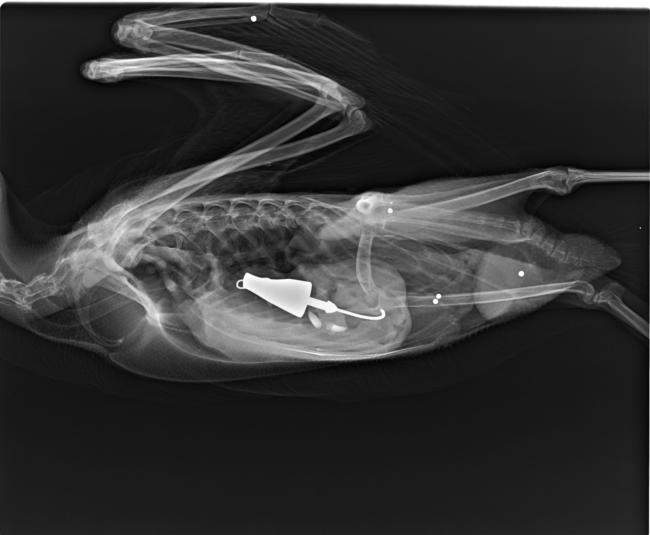

Many species of wildlife are exposed to lead in the environment, sometimes with devastating consequences. Some impacts are highly visible and well-documented, but many lesser-known species may be heavily impacted by lead poisoning too. Active surveillance is used to minimize the harms of lead poisoning, particularly in children. We aim to develop a system of active surveillance for lead poisoning in wildlife based on wildlife rehabilitation patients and hunter-harvested waterfowl.